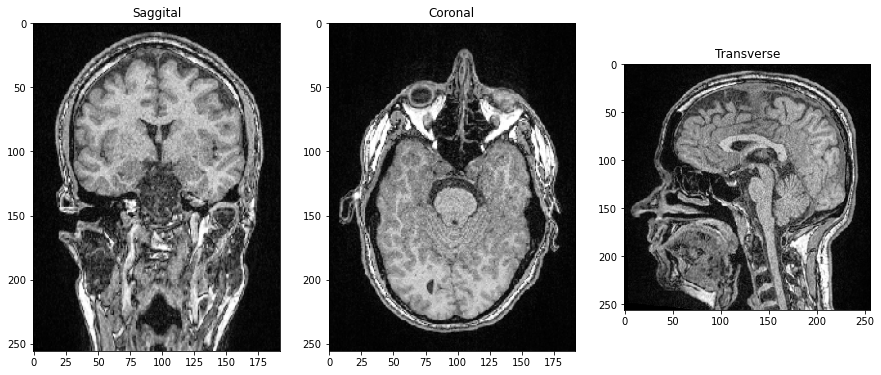

Il existe également des images avec trois dimensions spatiales : X, Y et Z. On trouve des exemples typiques en microscopie et en imagerie médicale. Examinons un ensemble de données d’Imagerie par Résonance Magnétique (IRM) :

Nous voyons que les données ont effectivement trois dimensions, dans ce cas 192 plans Z et 256 pixels X et Y. Nous pouvons l’afficher avec imshow de pyclesperanto :

imshow(image_stack)

Cet ensemble de données IRM semble inhabituel, car nous regardons une projection d’intensité maximale qui est la façon par défaut de pyclesperanto de visualiser des données tridimensionnelles.